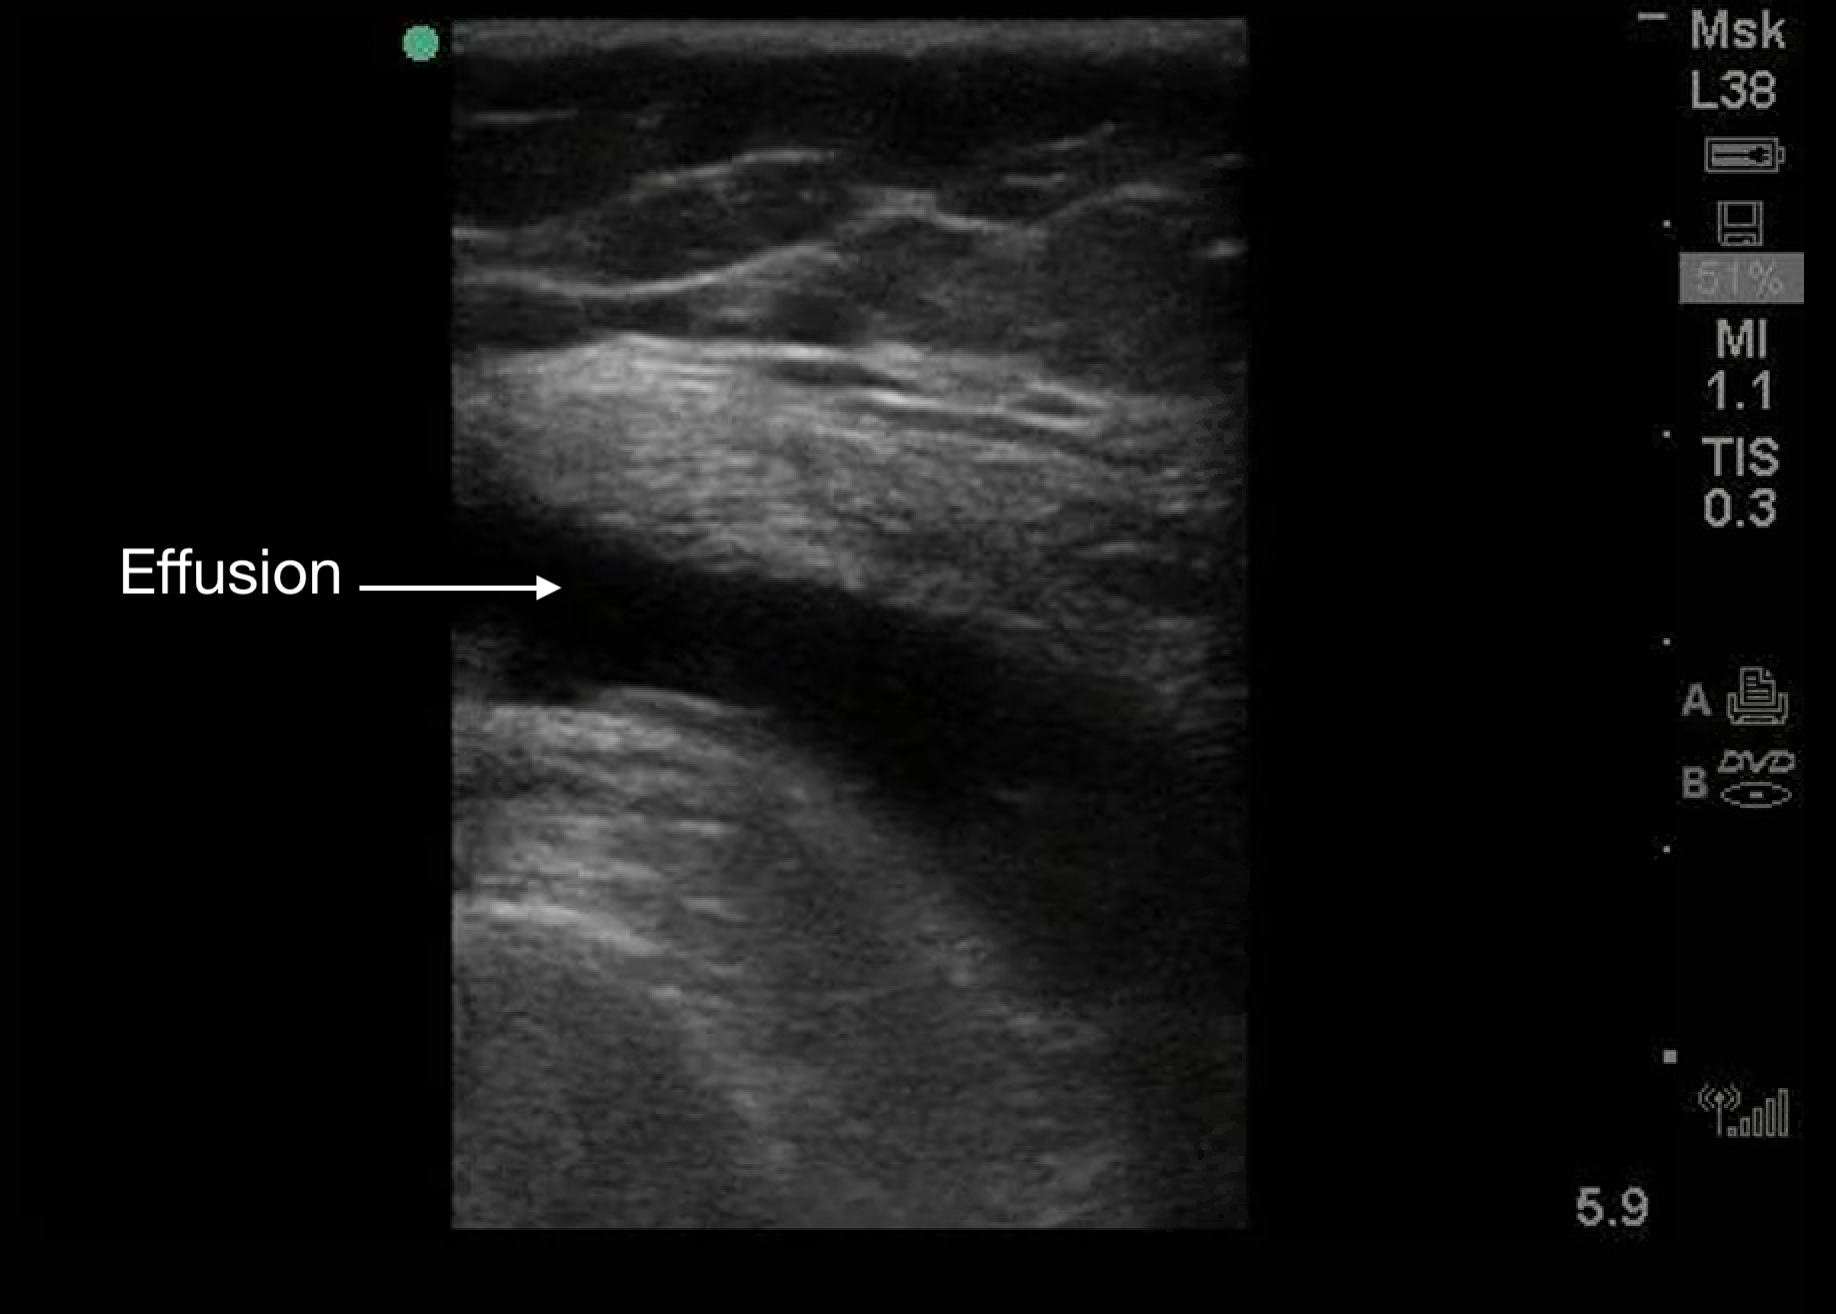

Appear as black (anechoic) areas within the joint space on ultrasound.

Figure 8.

A knee effusion seen with a linear transducer. Transducer positioning is the same as Figure 2C.